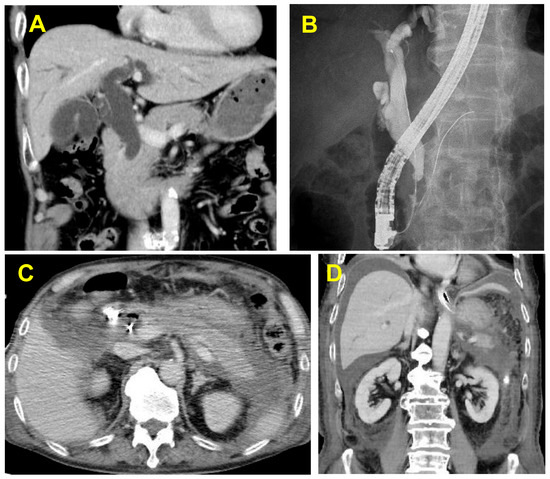

Notably, AI has demonstrated considerable promise in improving the early detection of Barrett’s neoplasia and colonic precancerous lesions. Similarly, the expanding role of endoscopic ultrasound (EUS) is redefining the management of malignant obstructions, offering both diagnostic precision and therapeutic utility. Innovations in small bowel capsule endoscopy have contributed to reduced reading times while maintaining strong diagnostic performance. Furthermore, bariatric endoscopy is emerging as a minimally invasive and effective strategy in weight management, with important clinical implications.

This Special Issue, "Advances in Gastrointestinal Endoscopy: From Diagnosis to Therapy", will showcase cutting-edge developments across the endoscopic spectrum, from foundational techniques in gastroscopy and colonoscopy to advanced procedures including ERCP, therapeutic EUS, AI-enhanced imaging, and bariatric endoscopic interventions.